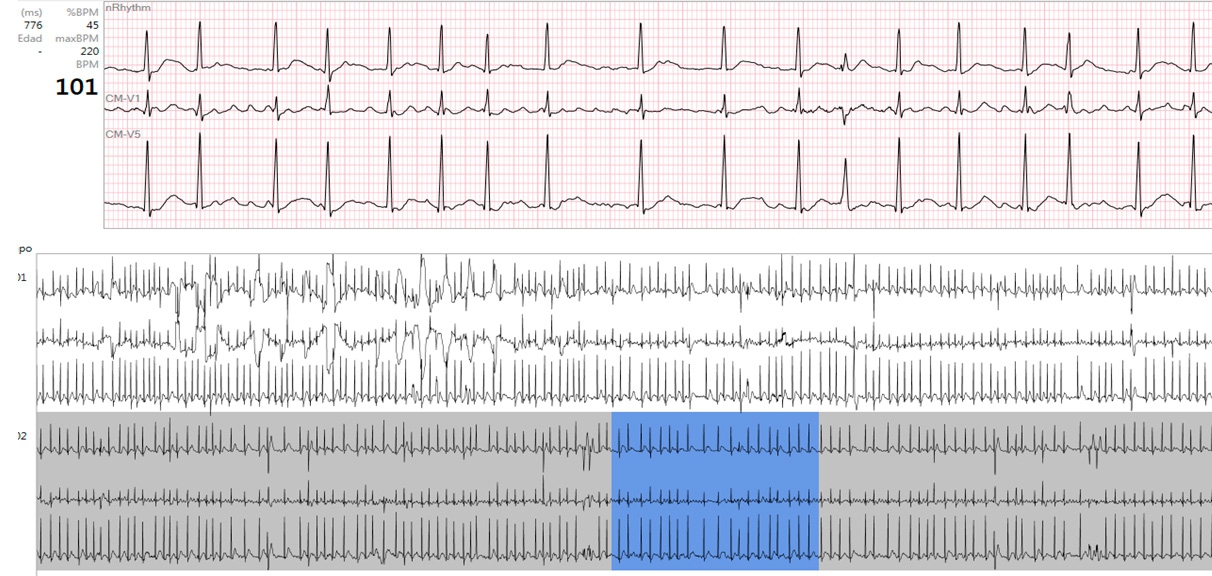

Patient 1 case: Atrial Fibrillation (II of IV) AF onset